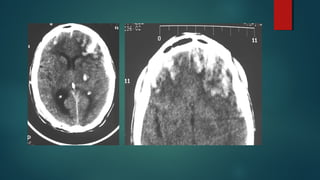

Este documento es el programa para un taller de imágenes del curso de emergencia 2015 impartido por el Dr. Víctor Delgado. El taller se centra en el uso de imágenes médicas para el diagnóstico y tratamiento de pacientes en coma traumático según la base de datos de Marshall. El Dr. Delgado es el único instructor repetido a lo largo del documento.